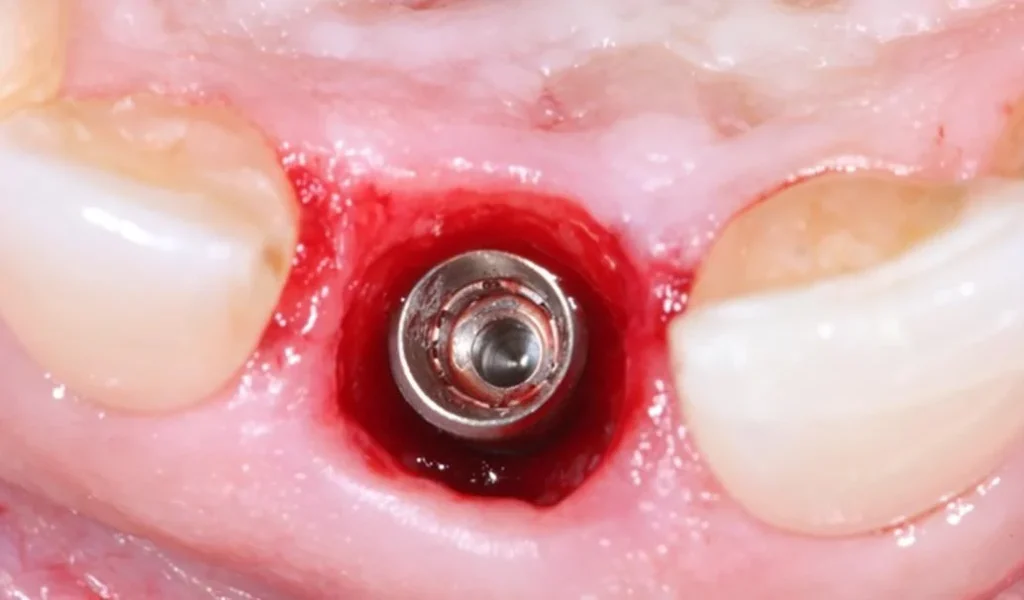

Step 2: Implant placement.

Once the guide and healing abutment are manufactured, the patient will be scheduled for surgery. Thanks to the guide, implant placement with Digital Customized Technology is usually quick and gentle. This is the second appointment, typically about 3 days (36 hours) after the first appointment.

Step 3: Placement of the customized healing abutment.

The customized healing abutment may be placed immediately after implant placement (in most cases) or during a second stage once the implant is stable. If placed in the second stage, another appointment will be required, typically 2–4 months after implant placement depending on the implant type.

Most cases have the healing abutment placed during implant surgery, which is an advantage of the solution because it reduces the number of surgical procedures.